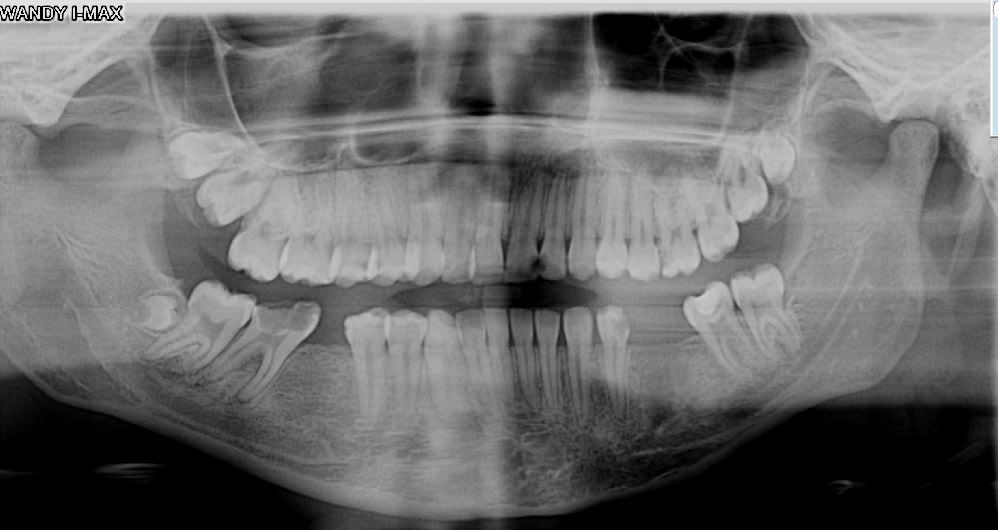

Dents de Super Sagesse :-))

Voir des 19/29 plus rarement 39/49 c'est pas non plus si exceptionnel ..

Dans la même veine, souvent à la pano découverte fortuite de prémolaires mandibulaires surnuméraires incluses.